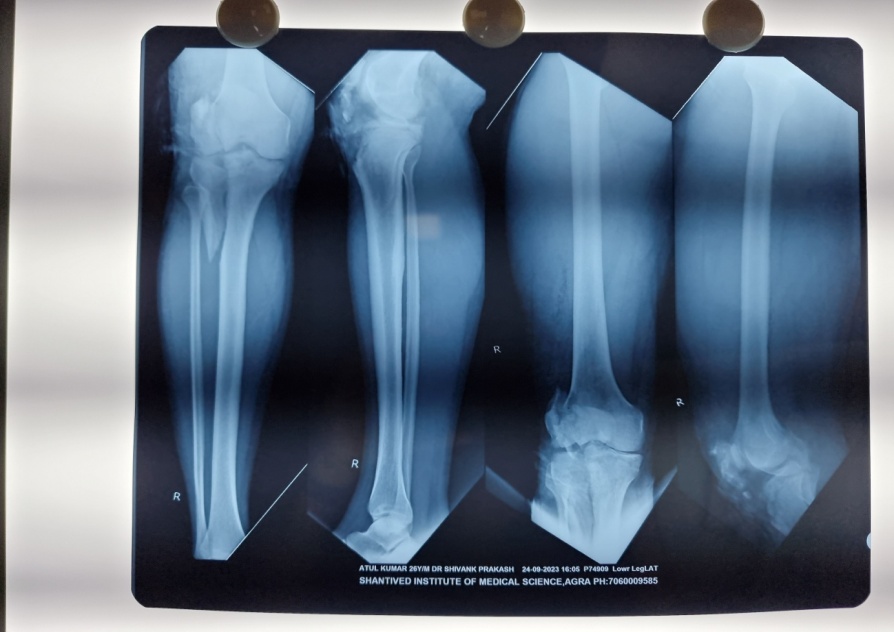

A 26 y-old male sustained a Type IIc Fraser and Type IVb Agarwal and Singh Floating knee injury on the right side. This included displaced intra-articular fractures of the lateral femoral condyle and lateral tibial plateau, a displaced patellar fracture with Grade II ACL tear and PCL sprain, complex tear of the lateral meniscus, and extensor mechanism rupture. Treatment involved external fixation for ipsilateral shaft fractures of the femur and tibia, along with a physiotherapy rehabilitation protocol for associated soft tissue injuries and tension band wiring for the patellar fracture. The patient achieved a good functional outcome after 2 y of follow-up, as depicted in [fig. 1a-d].

Fig. 1a: Preoperative X-ray AP and lateral view of 26 y old male having type IIc fraser and type IVb agarwal and singh floating knee injury

Fig. 1b: Postoperative X-ray at 6 mo follow-up